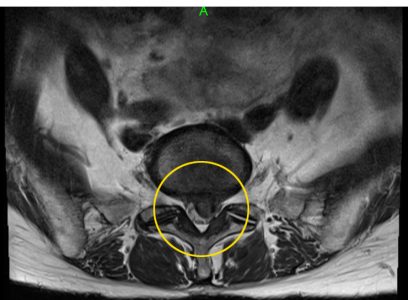

脊柱管の半分以上を覆う腰椎椎間板ヘルニア

脊髄中枢神経にめり込む椎間板ヘルニア